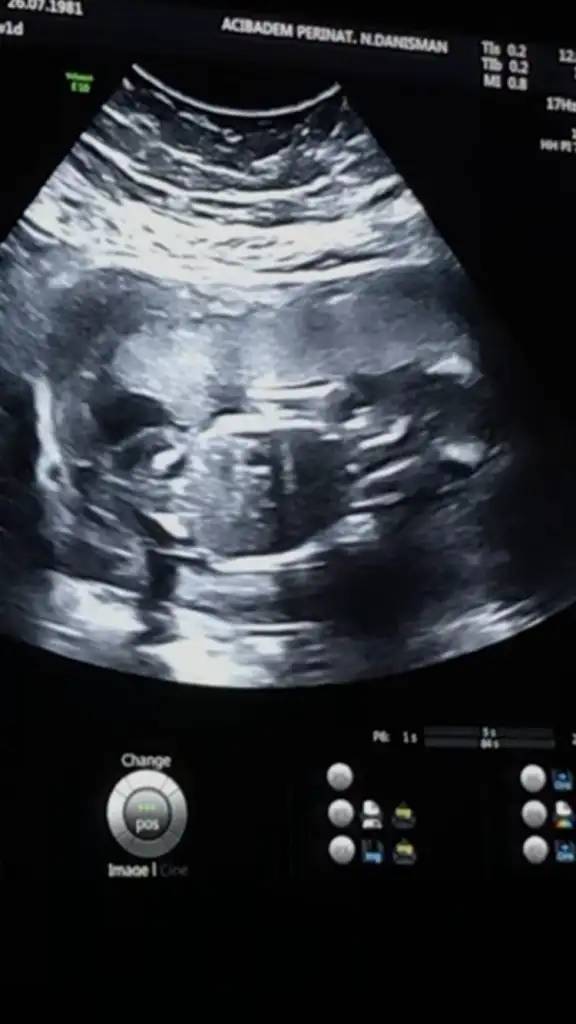

Doktor 99% erkek, ama degisme ihtimali var, 3 hafta sonra kesinlestiririz dedi. Normalde 16+2 ama 17+6 ciktik.

Gelisimi, vs her sey iyi. İkili istemedin, digerlerine de gerek yok dedi. 22. Haftada 2. detayli usg yapariz dedi.![]()